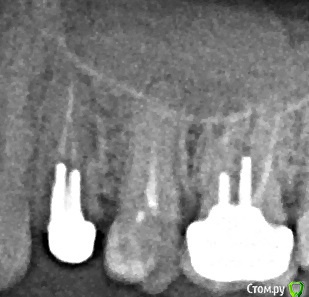

Scrabble Опубликовано 6 июня, 2015 Поделиться Опубликовано 6 июня, 2015 Имплантат всегда можно. Завтра поинтересуйтесь, когда именно. И обратите внимание на пазуху-там есть пролиферативный процесс(скорее всего, одонтогенный) Спросите врача, не стоит ли посетить лора. Ссылка на комментарий

Юми Опубликовано 6 июня, 2015 Автор Поделиться Опубликовано 6 июня, 2015 Есть еще такой снимок, от ЛОРа, правда с наложением Ссылка на комментарий

Юми Опубликовано 6 июня, 2015 Автор Поделиться Опубликовано 6 июня, 2015 Пожалуй, заеду завтра еще к ЛОРу, у меня воспаление как-то вверх пошло, на гайморову пазуху нажимать больно(( Ссылка на комментарий